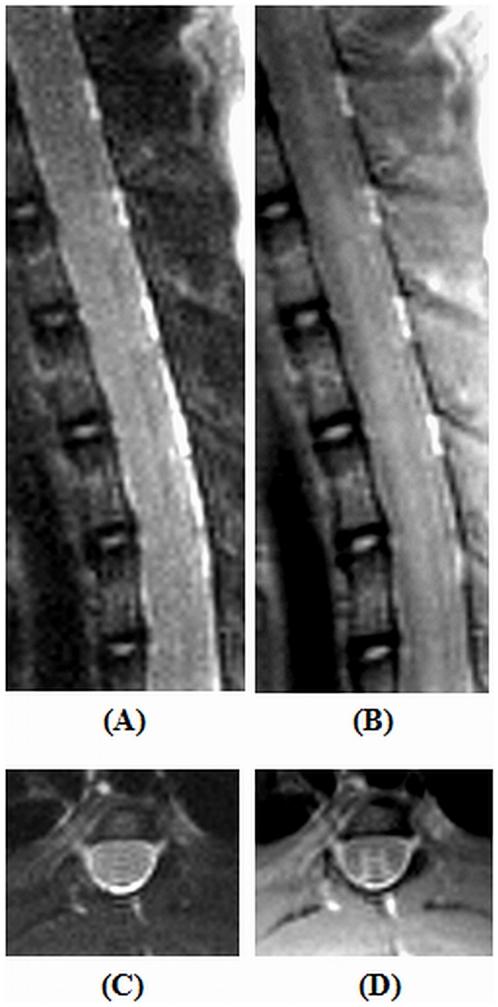

This study attempts to configure and optimize a clinical 3 Tesla magnetic resonance scanner to facilitate imaging of small animal central nervous system pathologies. The hardware of the scanner was complemented by a custom-built, 4-channel phased array coil system. Extensive modification of standard sequence protocols was carried out based on tissue relaxometric calculations. Proton density differences between the gray and white matter of the rodent spinal cord along with transverse relaxation due to magnetic susceptibility differences at the cortex and striatum of both rats and mice demonstrated statistically significant differences. The employed parallel imaging reconstruction algorithms had distinct properties dependent on the sequence type and in the presence of the contrast agent. The attempt to morphologically phenotype a normal healthy rat brain in multiple planes delineated a number of anatomical regions, and all the clinically relevant sequels following acute cerebral ischemia could be adequately characterized. Changes in blood-brain-barrier permeability following ischemia-reperfusion were also apparent at a later time. Typical characteristics of intra-cerebral haemorrhage at acute and chronic stages were also visualized up to one month. Two models of rodent spinal cord injury were adequately characterized and closely mimicked the results of histological studies. In the employed rodent animal handling system a mouse model of glioblastoma was also studied with unequivocal results.

本研究试图配置和优化临床 3 特斯拉磁共振扫描仪,以方便对小动物中枢神经系统病变进行成像。扫描仪的硬件由定制的 4 通道相控阵线圈系统补充。根据组织弛豫计算,对标准序列协议进行了广泛的修改。在大鼠和小鼠的皮质和纹状体中,由于磁化率差异导致的横向弛豫,对啮齿动物脊髓的灰质和白质之间的质子密度差异进行了广泛的测量,结果显示存在统计学上的显著差异。所采用的并行成像重建算法具有依赖于序列类型和存在对比剂的不同特性。试图在多个平面上对正常健康大鼠的大脑进行形态表型分析,描绘了许多解剖区域,并且可以充分描述所有与临床相关的急性脑缺血后的后续情况。缺血再灌注后血脑屏障通透性的变化在稍后时间也变得明显。在急性和慢性阶段的颅内出血的典型特征也可以在一个月内进行可视化。两种啮齿动物脊髓损伤模型也得到了充分的描述,并与组织学研究的结果非常相似。在采用的啮齿动物处理系统中,还对胶质母细胞瘤的小鼠模型进行了研究,结果明确。